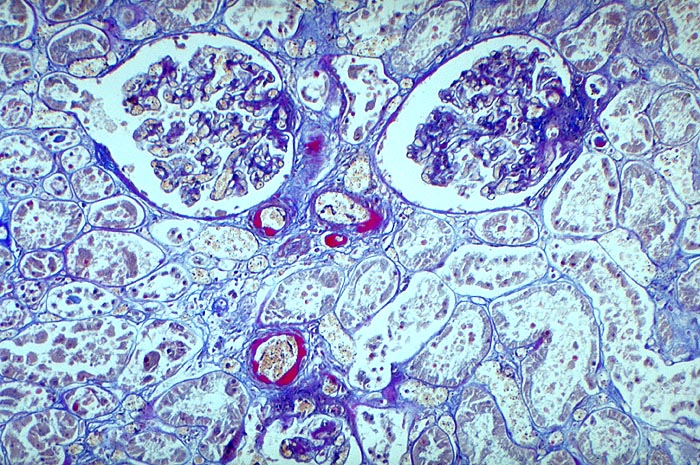

PathoPic – image database / PathoPic ID 1911 - Arteriolosklerose von Vas afferens und Vas efferens bei Diabetes

Arteriolosklerose von Vas afferens und Vas efferens bei Diabetes

Plumpe subendotheliale Proteinablagerungen von roter Farbe in den Arteriolen.

Typisch für Diabetes mellitus ist der Befall von Vas afferens und efferens, oft auch der Vasa recta. In intrarenalen Arterien unspezifische Atherosklerose teilweise mit Atheromen (typisch für Diabetes). Der Schweregrad korreliert im allgemeinen mit dem Ausmass der exsudativen Läsionen der Glomerulosklerose. Die Arteriolosklerose im Vas afferens beim Diabetes ist identisch mit der Arteriolosklerose bei arterieller Hypertonie.